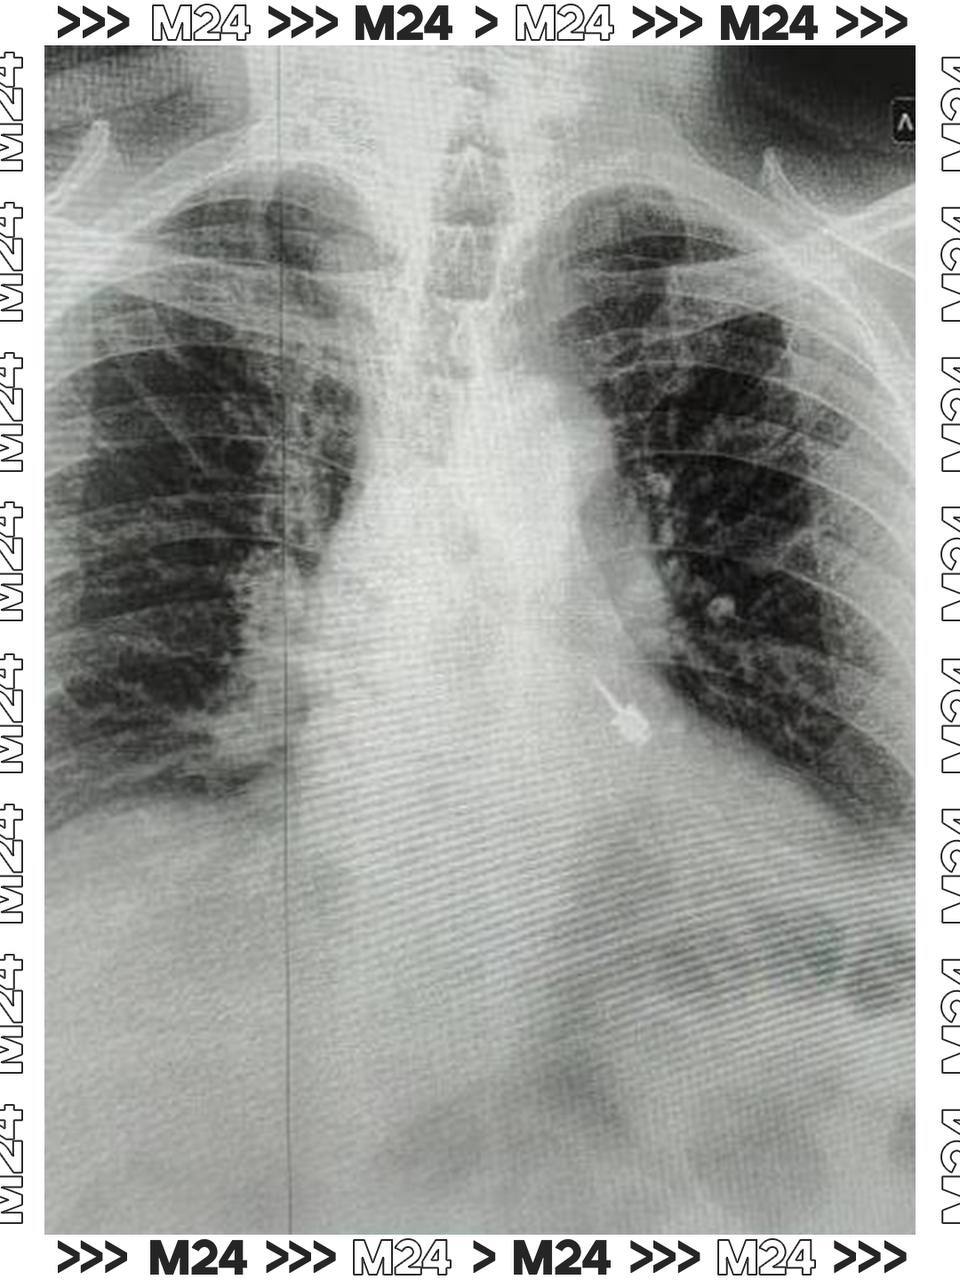

Он сразу почувствовал боль и отправился в больницу. Рентген показал, что бур находится в левом бронхе. Врачи Мытищинской больницы экстренно прооперировали пациента.

Главная задача, по словам медиков, заключалась в том, чтобы сделать это максимально аккуратно. Острая часть могла повредить стенки бронха, вызвав кровотечение или перфорацию.